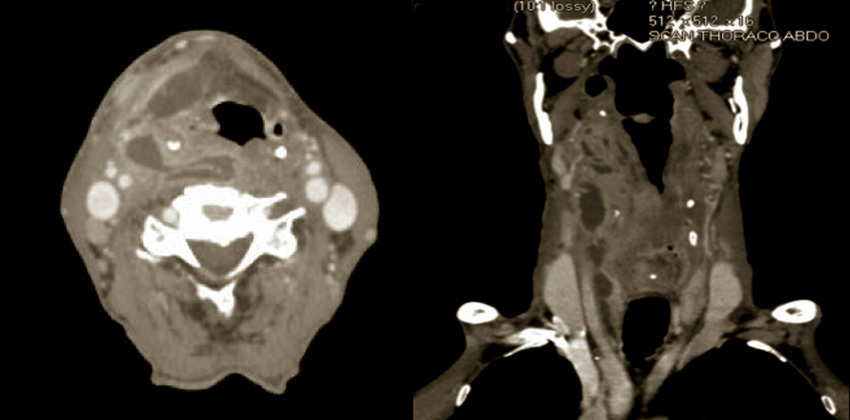

TDM cervicale avec injection de produit de contraste montrant les collections cervicales droites (hypodensité centrale entourée d'une hyperdensité périphérique).